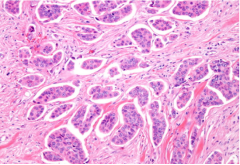

病理检查在确诊乳腺癌中扮演了重要角色。通过乳腺组织活检,医生可以确认癌症的类型和阶段,这些信息对治疗方案和预后判断至关重要。

图为乳腺癌组织活检病理切片